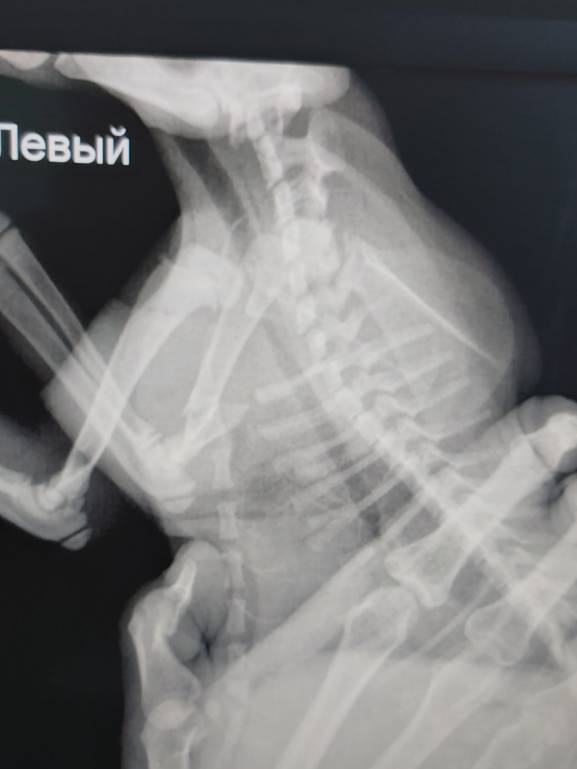

Сегодня на октябрьском был найден котенок. Он упал с 4 этажа и сломал лапу. Малыш очень сильно плачет, ему очень больно. Перелом в таком месте, что даже фиксирующую повязку трудно наложить.

Для лечения, пока перелом еще свежий, надо СРОЧНО в клинику. Мало того, не известно еще, кто сможет нам помочь - комсомольская фауна или хабаровский Бетховен. Те снимки, которые мы смогли сегодня сделать не дают полной картины. Надо делать еще один снимок под наркозом. А на это надо денег. Денег нет совсем.